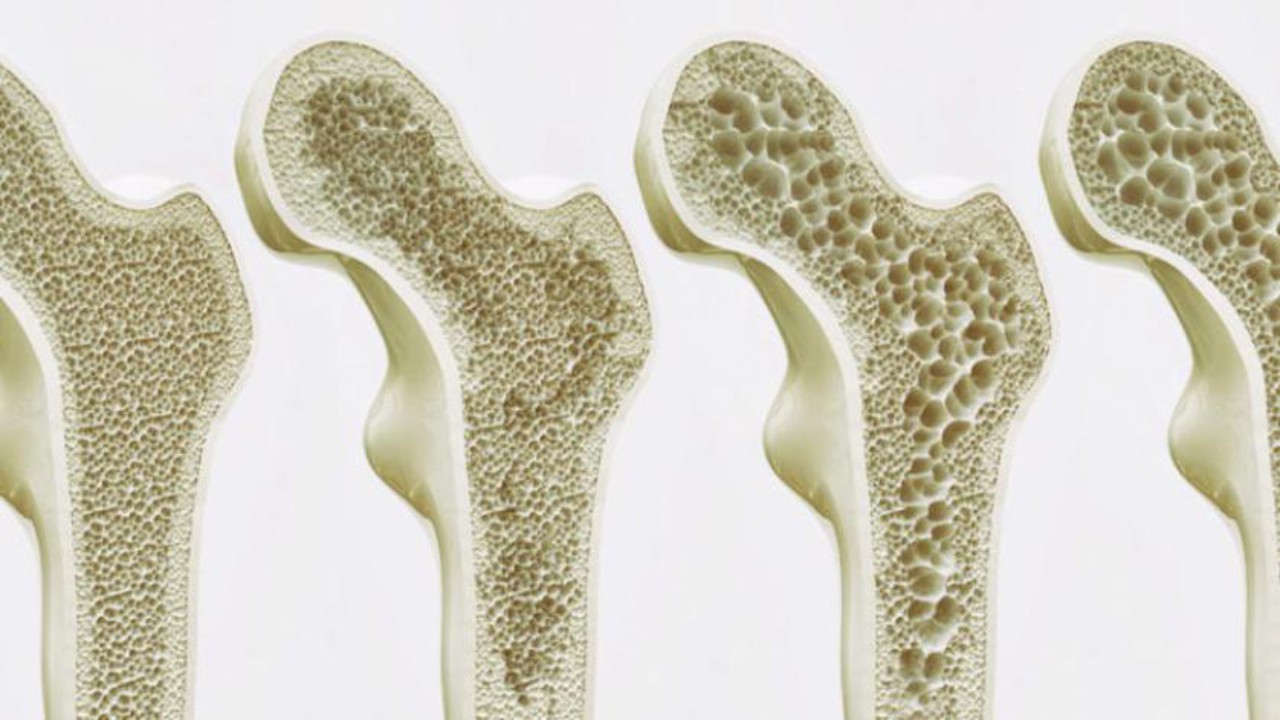

العلامات الأولى هشاشة العظام

تلوث الهواء يسرع هشاشة العظام وإصابات العمود الفقري